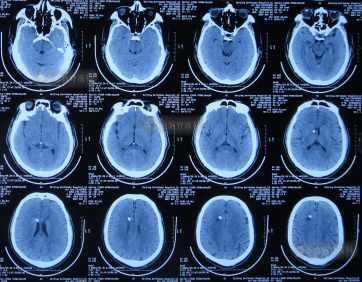

2021年9月4日(入院第7天),头颅CT示脑室明显缩小(图-9)。

图-9:2021年9月4日头颅CT

2021年9月15日(入院第5天),进行了脑室腹壁外引流术(图-10)。

图-10:2021年9月15日头颅CT